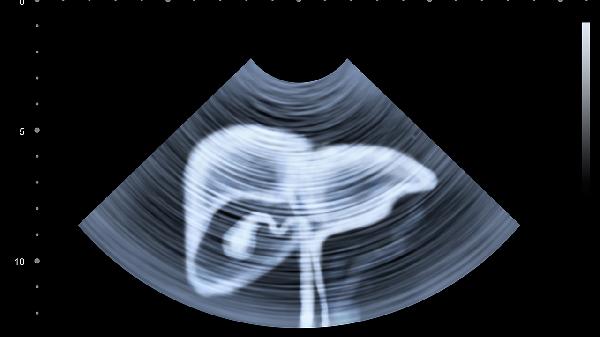

胆囊炎、附件炎等慢性炎症可能在跑步时因脏器震荡加剧疼痛,表现为右上腹或下腹固定位置钝痛。需就医完善超声检查,确诊后可遵医嘱使用消炎利胆片或甲硝唑片治疗,急性发作期需禁运动。